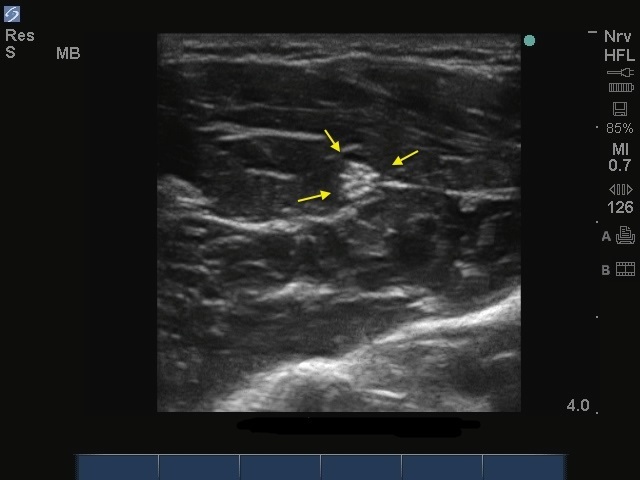

Bild: S-System, Nervus musculocutaneus

Pfeile: Nervus musculocutaneus